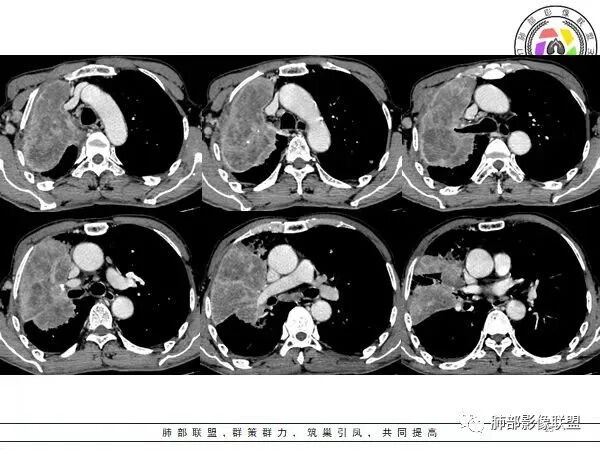

这个病例,看长轴、形态,首先跨叶,里面的坏死腔,它是相通的,就是跨中叶及前基底段。

如果是腔内的病变,第一,应该是局限在某个叶的,不可能上下叶都有。所以不太支持腔内的病变。因此考虑腔外的病变。腔外局限的肿瘤肯定不符合,假如这个病灶是个局限大肿块的话,里面肺动脉走势还可以。

然后中叶与下叶的坏死腔病灶是相通的,病灶是跨叶的,胸膜糊墙为主。

我要看一下下叶。还想重建一下,就是按照我自己理解的长轴去重建出这个病灶的整体形态,我当时一看,好像侧向融合的病灶。侧向融合的病灶考虑慢性炎性病变的,有几种,这样大片的病灶,常规都考虑特殊感染多一些,比如隐球,放线菌,奴卡等,都可以这样的改变。

现有的CT,里面存在坏死腔。炎症肯定有,是否同时合并肿瘤的问题?我需要详细的图将内部结构逐步剖析出来,看看能否有新的依据

南边:跨叶、楔形/边缘平直、支气管壁无破坏/连续/局部无膨大、实变区肺动脉走形自然、实性部分均匀、延迟强化、坏死腔内壁光滑/内壁强化环/近端与支气管相通,这些点均支持炎性。所以综合分析:符合炎性。